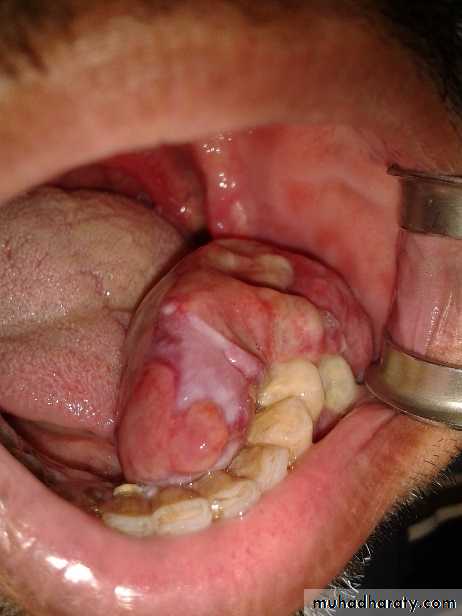

Ameloblastoma:-

It is a tumor arising from embryonal cells of developing teeth. Although most forms of this tumor simulate other slow-growing benign tumors some can develop malignant tendencies.Patient may have few subjective symptoms during tumor growth. Enlargement of the tumor may expand the buccal, lingual or palatal bone plates. Tooth may be loosen and pressure symptoms may occur.

Raioraghical examination may demonstrate unlocular or multilocular types. Unilocular ameloblastomas may be confused with benign cysts. The tumors frequently absorbs the alveolus surrounding ,the roots of teeth and may absorb root ends.

Ameloblastoma grow by extension into adjacent tissues and may perforate the investing bone. A biopsy should precede treatment since

these tumors frequently present with individual characteristics.